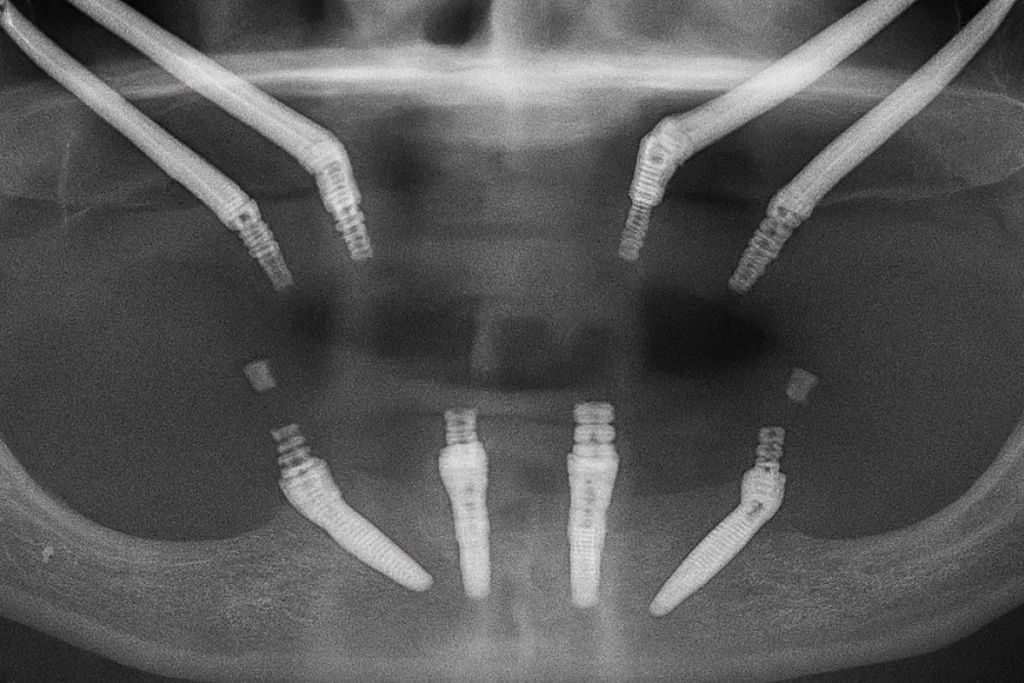

Immediate Restoration with Zygomatic Implants: A Reliable Solution in Costa Rica

Advanced implantology in Costa Rica has reached a level of specialization that ensures safe, functional, and aesthetically natural results, even in complex cases. Zygomatic implants represent one of the most innovative techniques in modern dentistry, offering an effective alternative to traditional bone grafts. This advanced approach allows for the immediate rehabilitation of patients with severe […]